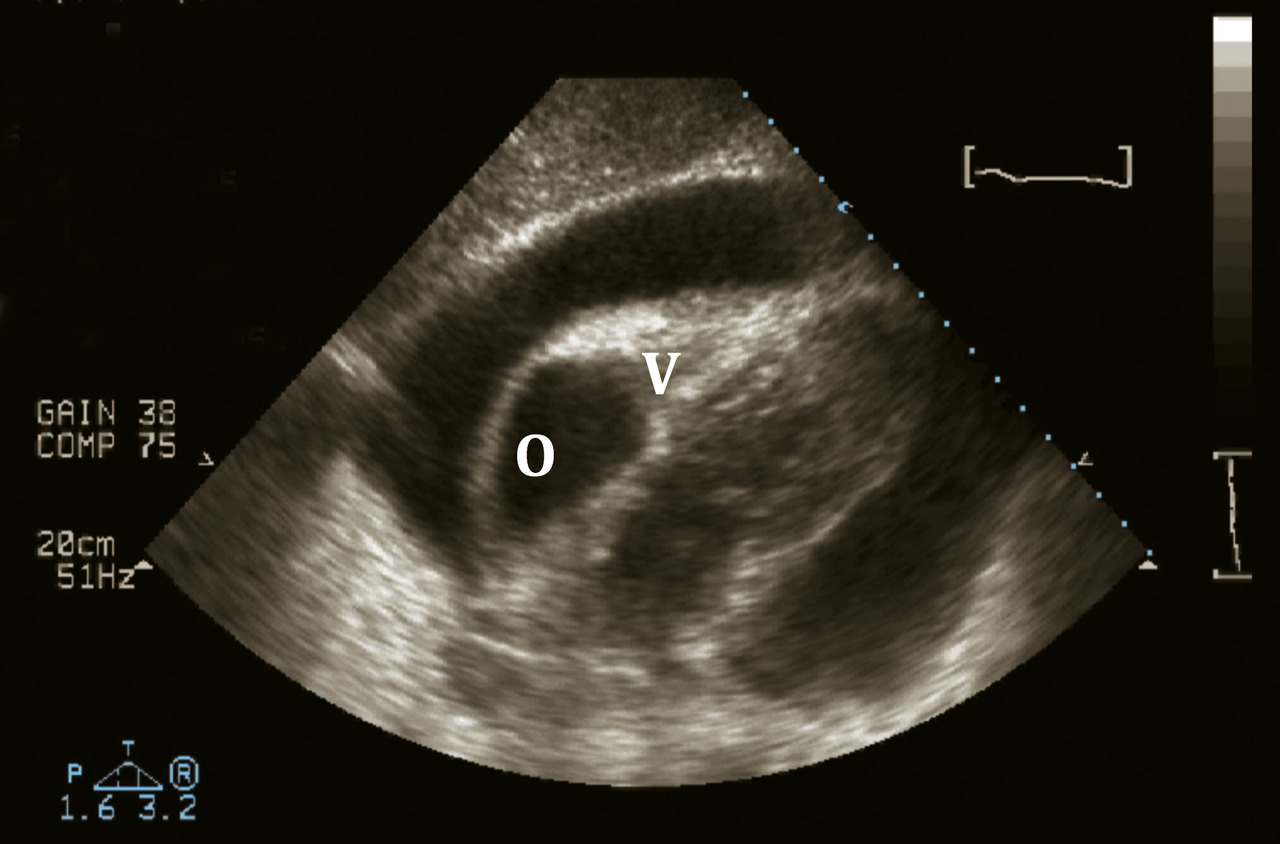

Échographie cardiaque

L’objectif est de rechercher un éventuel épanchement péricardique et de quantifier son importance et son retentissement sur les cavités cardiaques. Dans deux tiers des cas, on peut retrouver un décollement péricardique, le plus souvent minime (< 10 mm) et sans retentissement. Un épanchement significatif (> 20 mm) est rare, et doit faire rechercher une cause spécifique plutôt qu’une origine virale bénigne. Quelle que soit l’importance de l’épanchement péricardique, la compression des cavités droites constitue un tableau de tamponnade souvent accompagné de signes cliniques évocateurs (v. Examen clinique). Le retentissement de l’épanchement péricardique n’est pas lié à son importance mais à sa vitesse d’apparition, il n’y a donc pas de corrélation entre l’abondance de l’épanchement et son retentissement.

En dehors d’un éventuel épanchement péricardique, l’échographie est normale. Un trouble de cinétique segmentaire ou une altération de la fraction d’éjection doit faire suspecter un infarctus du myocarde ou une myocardite. Une fuite aortique doit faire rechercher une dissection aortique.

Tamponnade

La tamponnade correspond à la compression des cavités droites par un épanchement péricardique (fig. 3). Il s’agit d’une urgence médicale. Le diagnostic repose sur les signes d’insuffisance cardiaque droite : turgescence jugulaire, pouls paradoxal. Il peut y avoir des signes de choc : hypotension, vasoconstriction périphérique.

En échographie cardiaque, épanchement abondant avec reten­tissement sur les cavités cardiaques droites.